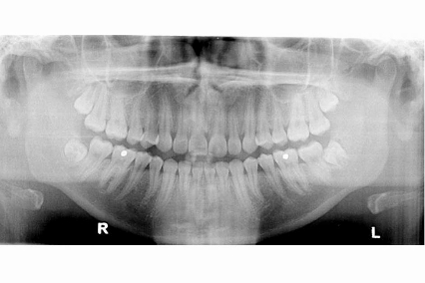

EXTRACTION DES DENTS DE SAGESSE À PIERREFONDS ET MONTRÉAL

L’extraction des dents de sagesse est l’une des procédures que nous pratiquons régulièrement. En effet les 3e molaires appelées communément dents de sagesse, sont souvent inutiles à la mastication. En raison d’un manque d’espace en bouche, les dents de sagesse ne font qu’une éruption partielle ou sont totalement incluses. Elles peuvent ainsi occasionner des complications. Votre dentiste saura vous conseiller si l’extraction préventive est indiquée.